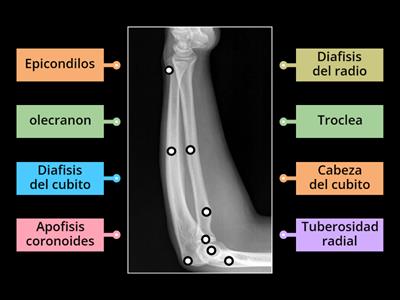

Anatomia Rx antebrazo ap